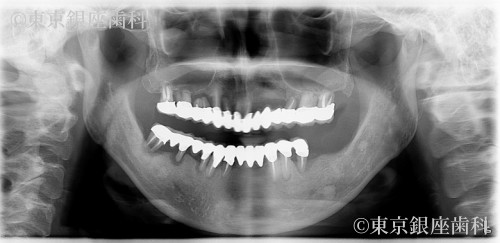

Before

過去の高額ブリッジ治療が数年で崩壊し不安を抱えて来院。部分インプラント後、上下ワンデイへ移行。サイナスリフトも併用し安定した噛み合わせを獲得。